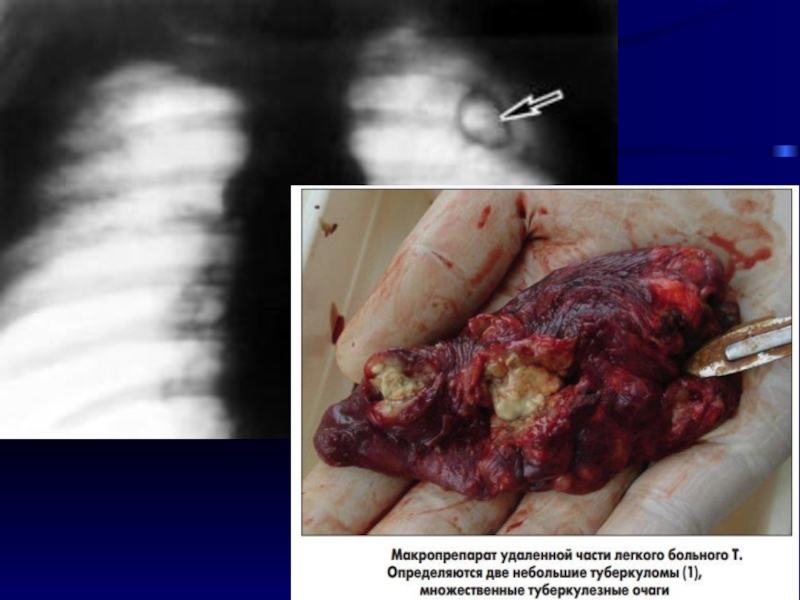

Слайд 995. Туберкулема

Округлый, ограниченный очаг > 1- 1,5 см, окруженный капсулой

R-ки

напоминает периферический рак легкого

5. Туберкулема Округлый, ограниченный очаг > 1- 1,5 см, окруженный капсулойR-ки напоминает периферический рак легкого